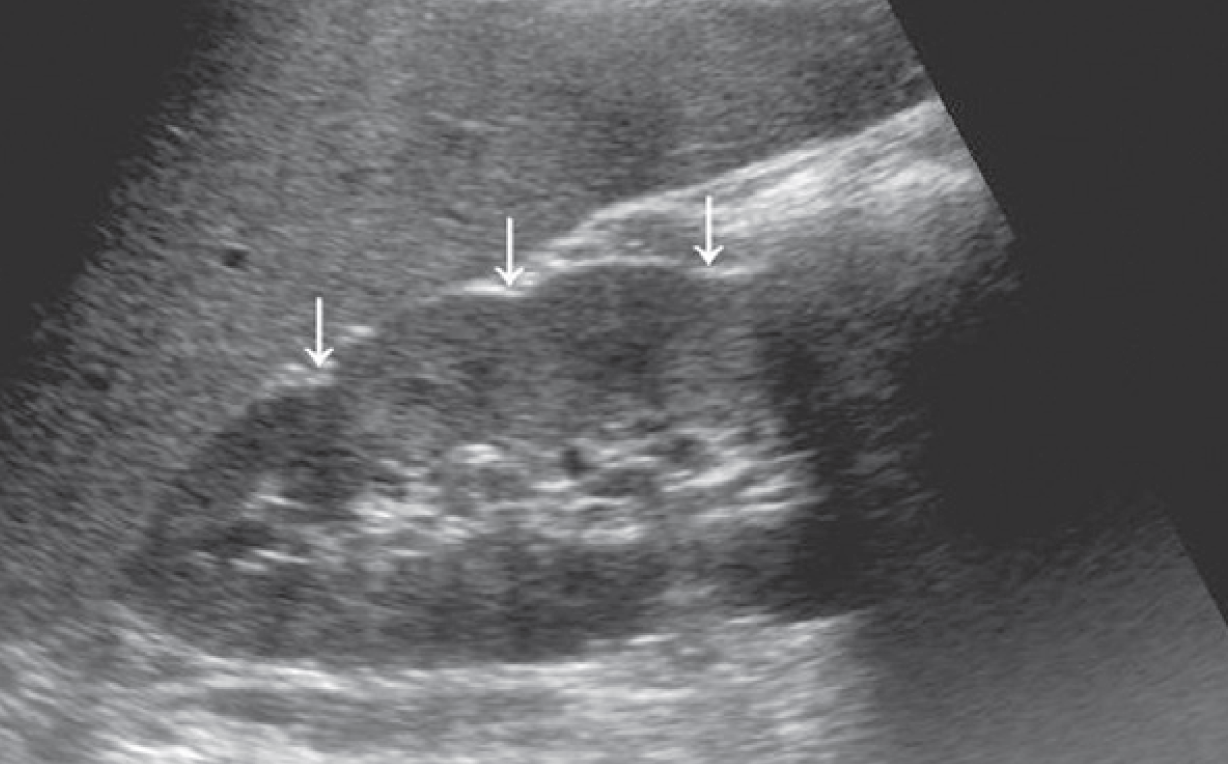

1-Hypertrophied column of Bertin

أعتقد بأن هذا من أهم المتغيرات التي قد يشتبه في كونها ورم. هي ببساطة تضخم لنسيج الكلية parenchyma إلى الداخل sinuses مرورا بين الأهرامات الكلوية medullary pyramids.

يميزه تناسق echogenicity بينه وبين باقي parenchyma بالإضافة لعدم وجود ارتفاع أو تغير ملحوظ في قراءات colour Doppler. غالبا لا يزيد عرضه عن ٣ سم.